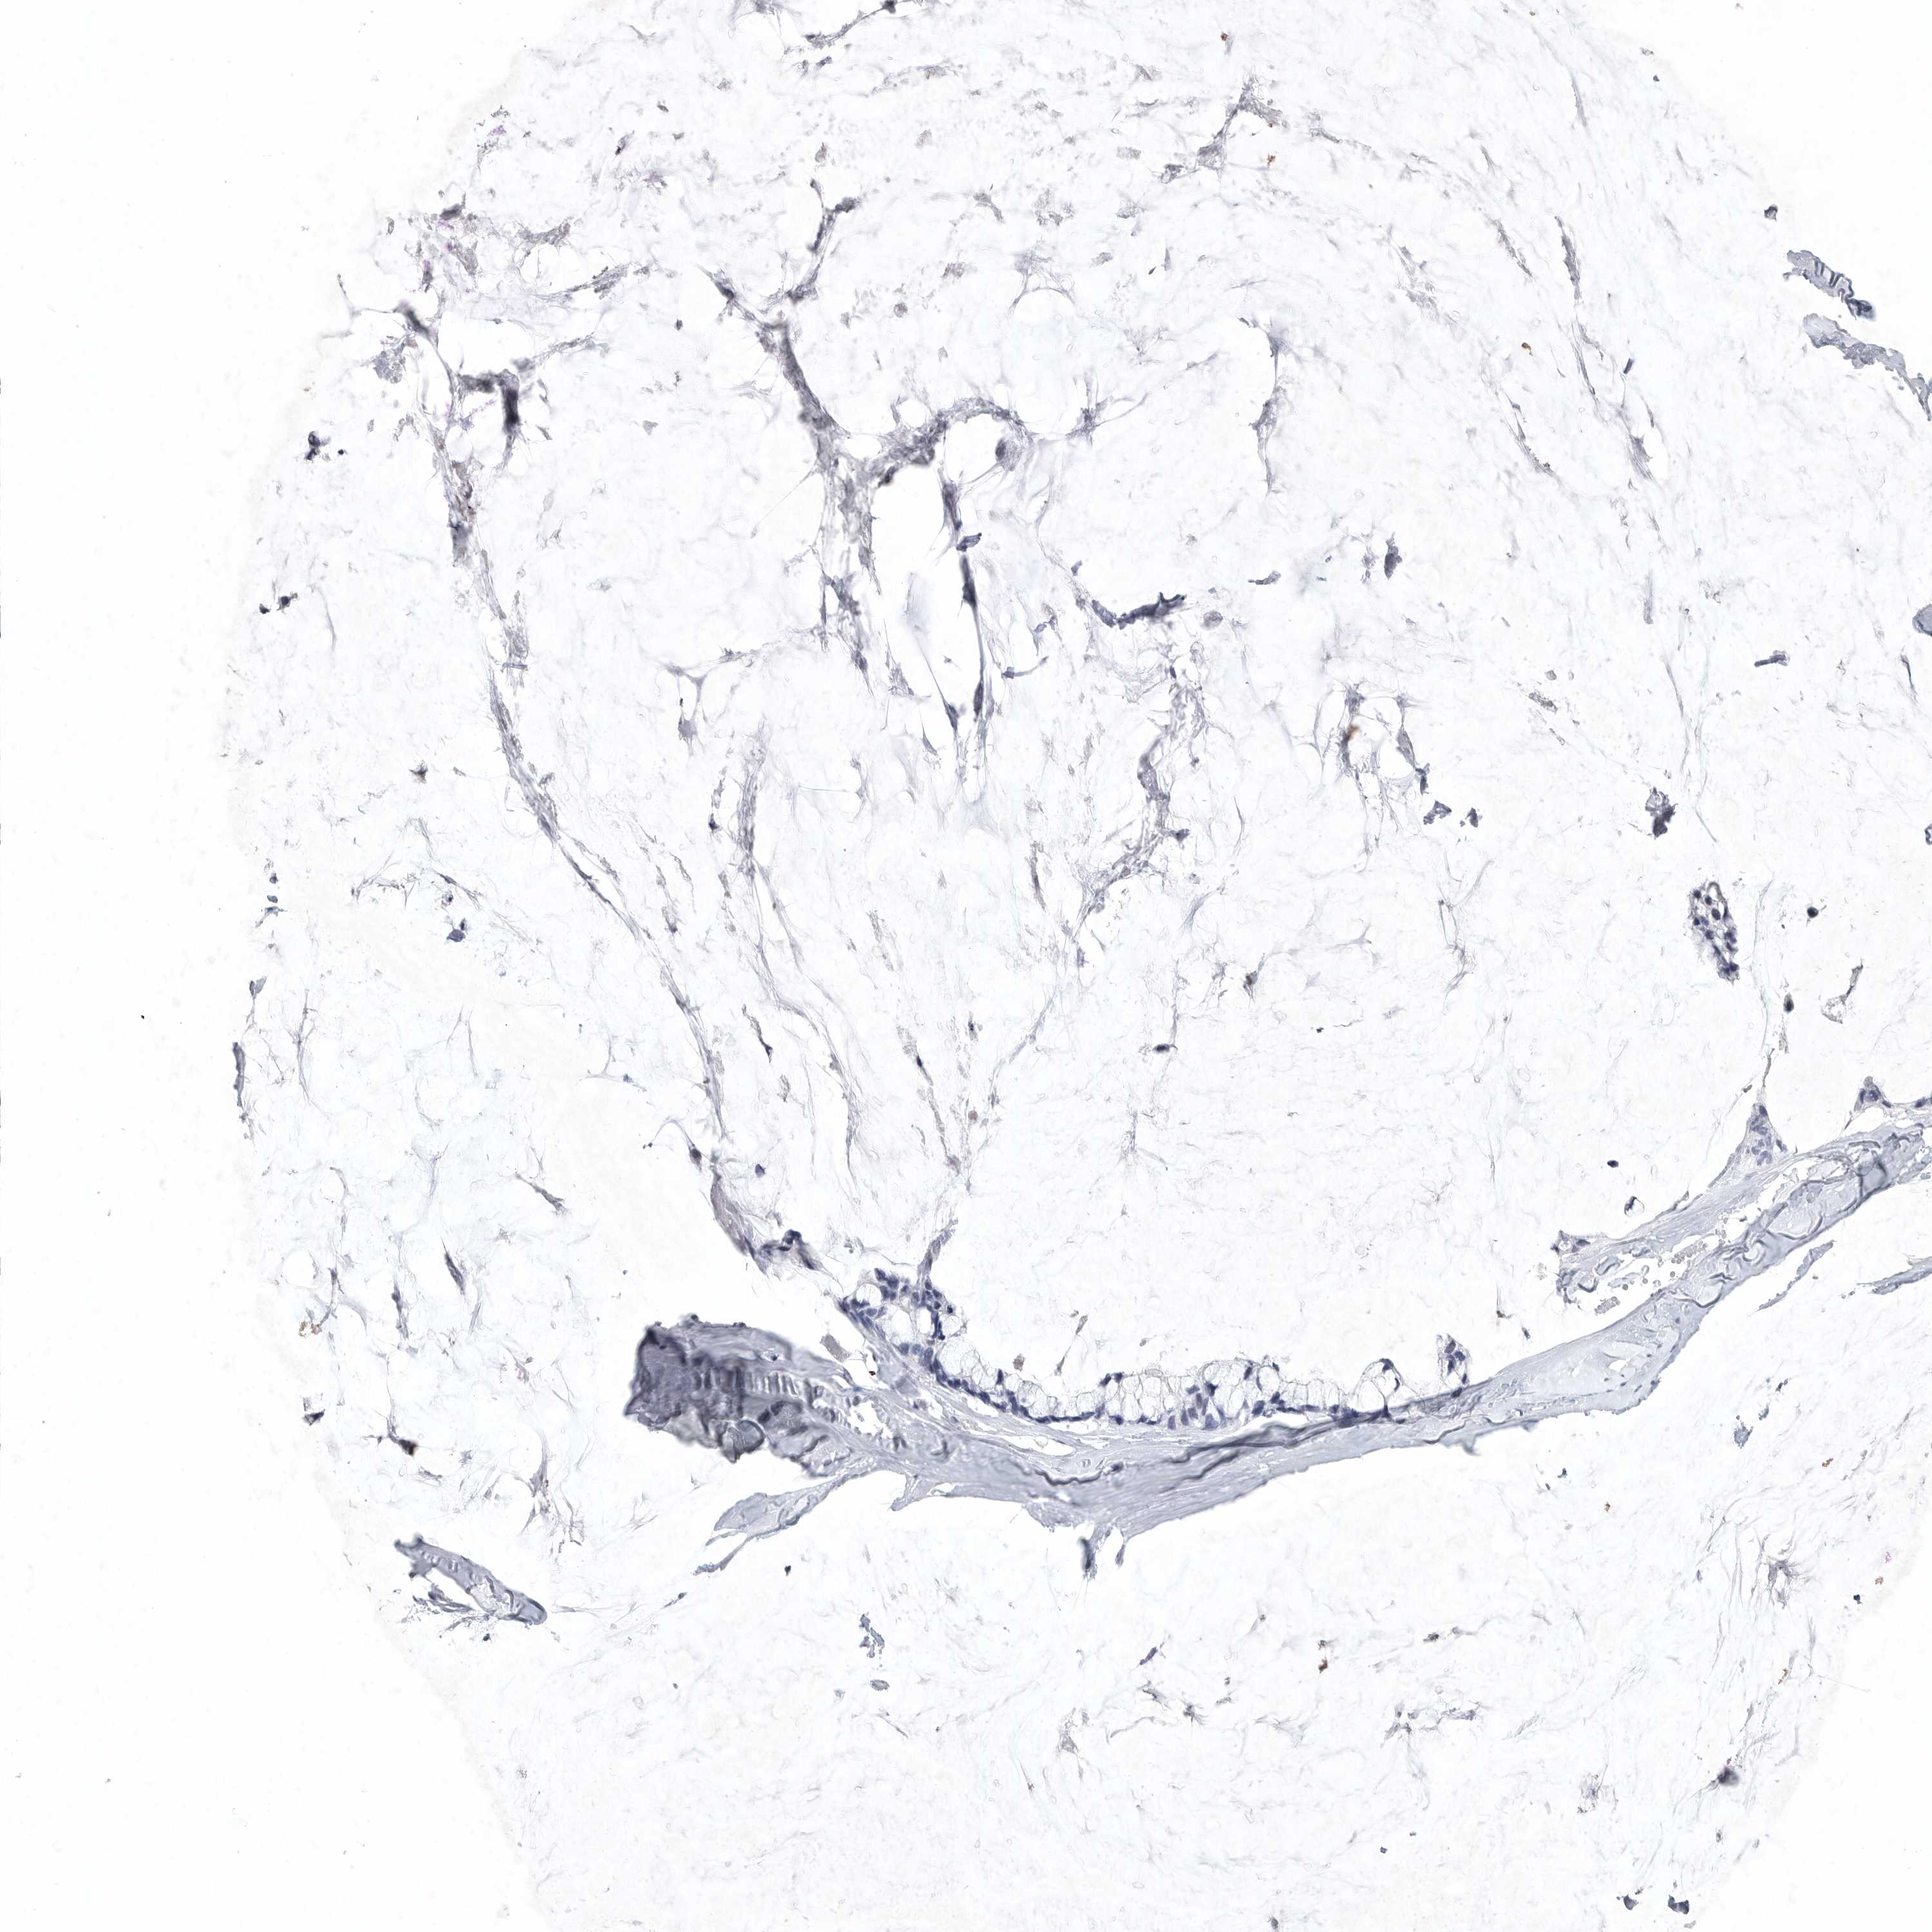

OVARIAN CANCER - Protein expressioni

A mouse-over function shows sample information and annotation data. Click on an image to view it in a full screen mode. Samples can be filtered based on level of antibody staining by selecting one or several of the following categories: high, medium, low and not detected. The assay and annotation is described here.

Note that samples used for immunohistochemistry by the Human Protein Atlas do not correspond to samples in the TCGA dataset.

Antibody stainingi

Antibody staining in the annotated cell types in the current human tissue is reported as not detected, low, medium, or high, based on conventional immunohistochemistry profiling in selected tissues. This score is based on the combination of the staining intensity and fraction of stained cells.

Each image is clickable and will lead to virtual microscopy that enables deeper exploration of all samples and also displays staining intensity scores, fraction scores and subcellular localization as well as patient and tissue information for each sample.

Antibody HPA027134

Antibody HPA027150

Antibody HPA029859

Antibody CAB022343

Staining

High

Medium

Low

Not detected

Intensity

Strong

Moderate

Weak

Negative

Quantity

>75%

75%-25%

<25%

None

Location

Nuclear

Cytoplasmic/membranous

Cytoplasmic/membranous,nuclear

Cystadenocarcinoma, serous, NOS

Carcinoma, endometroid

Cystadenocarcinoma, mucinous, NOS

Carcinoma, NOS